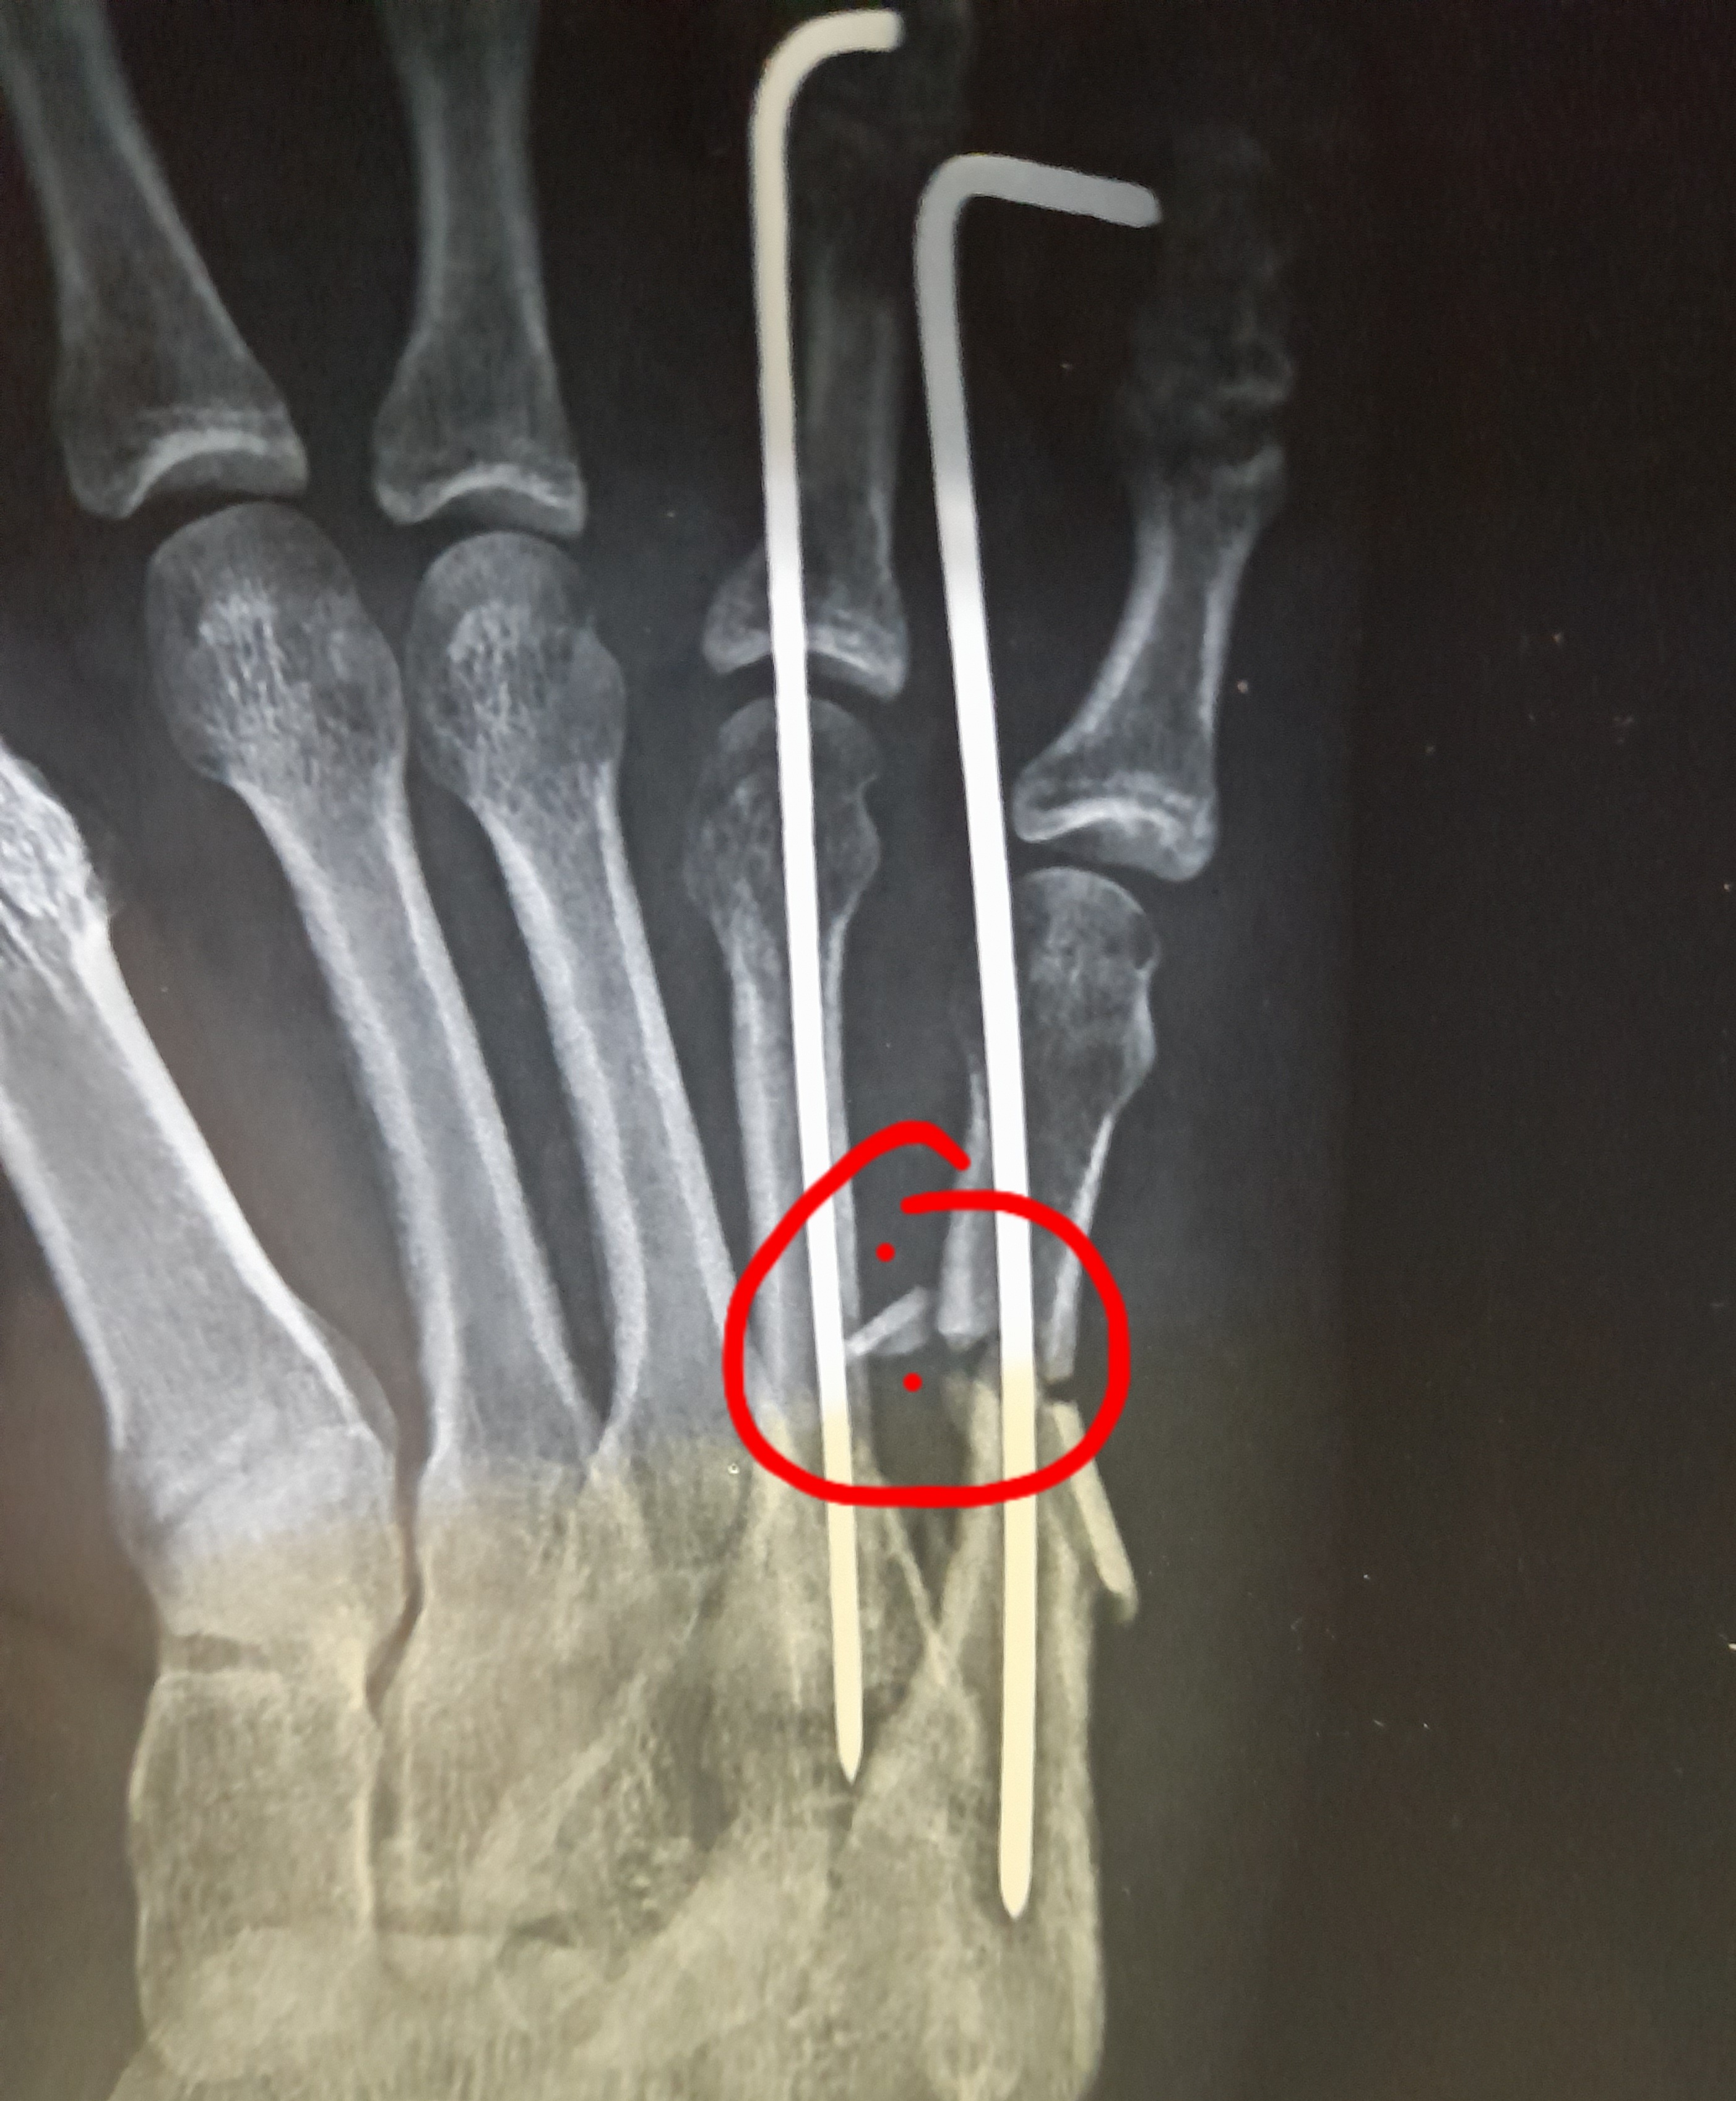

Operation should be perfect

Dr. Subair Khan, Orthopedist sir always Positive approach no problem in that but Sorry to say the treatment is not satisfying to me because more than 30 days I taken treatment in ORTHOMED and while doing operation they didn’t clear fractured bone piece inside the wound for that reason I got admitted in another hospital now and In orthomed especially from casualty department lots of miscommunication from nurses and duty doctors it was totally disappointed to me